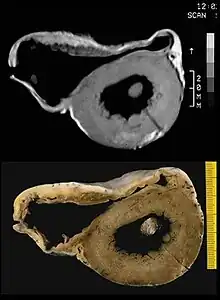

Arrhythmic cardiomyopathy pathology a) Right ventricular dilatation, anterior and posterior wall aneurysms b) transmural fibrofatty replacement c)focal subepicardial left ventricular involvement

In vitro MRI and corresponding cross section of the heart in ARVD show RV dilatation with anterior and posterior aneurysms (17-year-old asymptomatic male athlete who died suddenly during a soccer game).